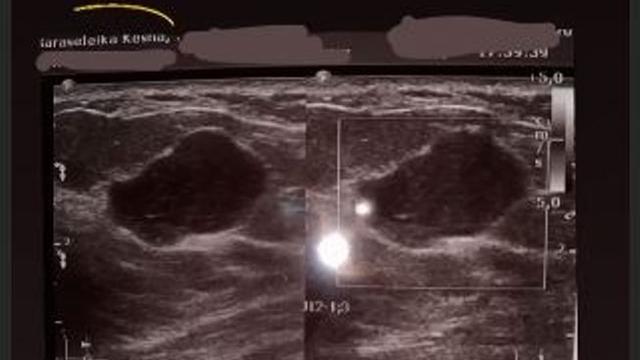

Dalam Instagram Story lainnya, Kesha Ratuliu mengaku itu bukanlah USG bayi dalam kandungannya. "Itu hasil USG payudaraku yang sebelah kanan," tambahnya.

"Kenapa ada lingkaran hitam yang kalian sangka itu janin. Itu adalah tumor/kista kenapa masih belum tau karna aku belum konsul kembali dengan dokter hehe," sambungnya.

Saat ini, tumor/kista yang dimiliki Kesha Ratuliu sudah mencapai tiga sentimeter.

"Aku adalah tipe yang kelenjar payudaranya besar besar jadi lebih gampang tumor atau kista tumbuh dipayudaraku.

Dan beruntungnya benjolan ini ada di arah jam 2 payudara kananku jadi aku tau lebih cepat kalo ada benjolan.

Dan setelah di check ternyata sudah 3 cm jadi lumayan besar menurutku," paparnya.